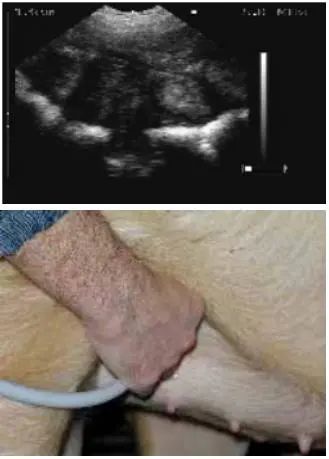

2.4 不同位置的扫描影像图

用B超进行妊娠鉴定时,应检测母猪身体的不同部位,以获得子宫内的详细情况,不同位置的扫描影像见图1、图2、图3、图4和图5。

图 1 位置1超声波影像图

图 2 位置2超声波影像图

图 3 位置3超声波影像图

图 4 位置4超声波影像图

图 5 位置5超声波影像图

在母猪腹股沟部,即腹部和后腿连接的三角区,最后两对乳头中间位置扫描检测。母猪有双孕角,左右两侧均可以检测。

⑴ 扫描仪的探头涂上耦合剂,置于探头检测位置。

⑵ 缓慢移动探头,直至看见清晰的胚胎影像。

⑶ 如果影像模糊不清晰,可在探头上涂抹更多的耦合剂。

⑷ 扫描没有发现胚囊或者胚囊较少时,可以在另一侧扫描。

⑸ 至少要看见3个不同的胚囊,才能鉴定为妊娠。